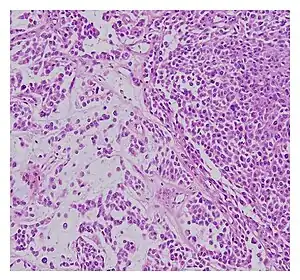

| Histopathological examination of malignant chondroid syringoma | |